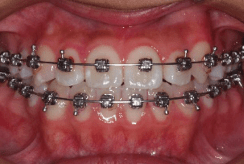

小児矯正で成長の誘導を行っても解決できない問題が残る場合は、永久歯が生えそろった後に改善が必要となります。永久歯が生えそろう中学生くらいから矯正治療をはじめることが多く、もちろん成人になっても矯正治療は可能です。ブラケットという固定式の矯正装置を使って歯をそれぞれ移動させ、きれいな歯ならびを完成させます。